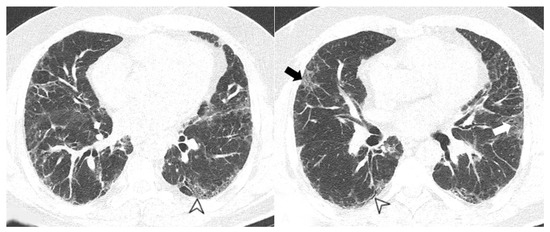

4.2.2. HRCT Findings of Patients with Anti-MDA-5 Abs

| Lesions | GGO, reticulations, consolidations | consolidations, GGOs | |

| Distribution | Homogeneous; lower lung lobes, along bronchovascular bundles and lung periphery; loss of volume of lower lobes | Patchy; peripheral lower lobes or along the bronchovascular bundles | |

| CT pattern | NSIP OP NSIP-OP UIP DAD-unclassifiable | 50% 20% 25% 10% +/− | 20% 50% 25% <5% ++ |